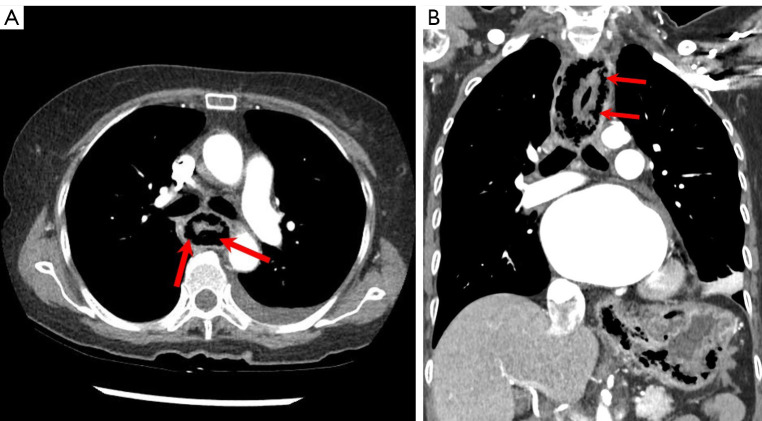

Case description: A 65-year-old woman was admitted to Inje University Sanggye Paik Hospital with general weakness, abdominal discomfort, nausea and chest discomfort. On chest and abdominal radiographs, there were abnormal air density in upper mediastinum and abdomen. Chest and abdomen computed tomography (CT) revealed mural air at entire esophagus and stomach. The patient managed with proton pump inhibitor (PPI), broad spectrum antibiotic therapy, and total parenteral nutrition (TPN).